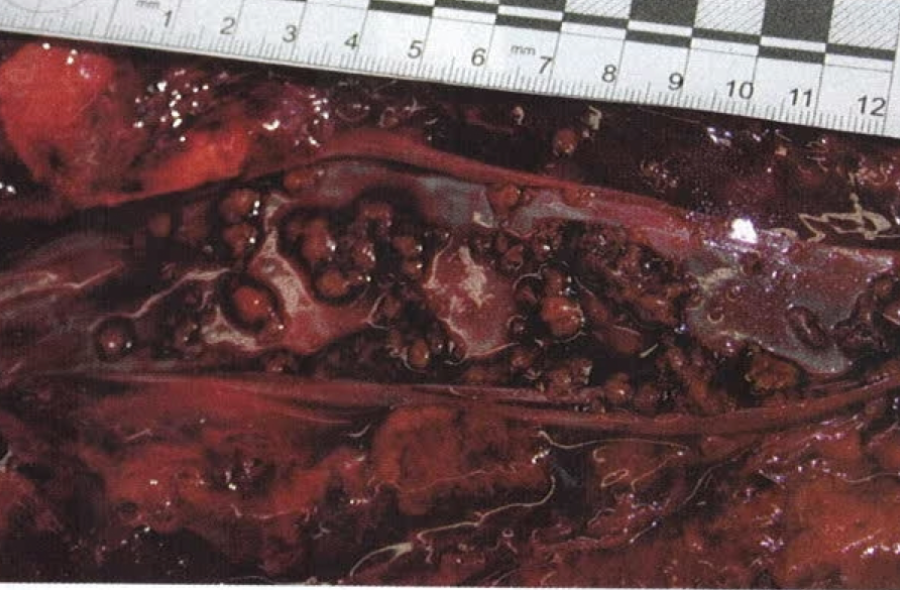

fat embolism 1 post gluteal lipoinjection